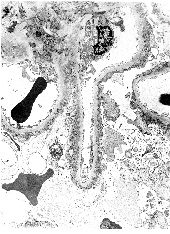

Glomerulopathy Associated with Lecithin-Cholesterol-Acyltransferase Deficiency: A Case Report and Literature Review

Clemence Delteil1,2*, Nicolas Macagno1, Romain Appay1, Marc Uzan3, Noemie Jourde-Chiche4,5, Laurent Daniel1,5